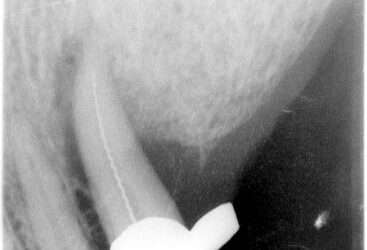

Nicht häufig gelingt es, eine Fistel röntgenologisch so sauber darzustellen wie in diesem Fall eines füllungs- und kariesfreien 14, der ohne nachvollziehbaren Grund plötzlich klopfschmerzhaft wurde, fistelte und einen Lockerungsgrad von L=I-II aufwies. Es dauert zwar...